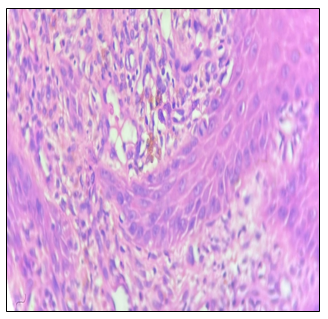

Pseudo-epitheliomatous hyperplasia, dermal infiltrate showing epithelioid granulomas, Acanthotic epidermis, ill-defined granulomas with Langans giant cells. Occasional cluster of thick walled, brownish spores/ sclerotic bodies were noted in the dermis 10% KOH mount: round, pigmented sclerotic bodies or “Medlar bodies”.

Figure 3 Pseudoepitheliomatous hyperplasia: Dermal infiltrate showing epithelioid granulomas.

Figure 4 Acanthotic epidermis: Ill-defined granulomas with lagans giant cells.